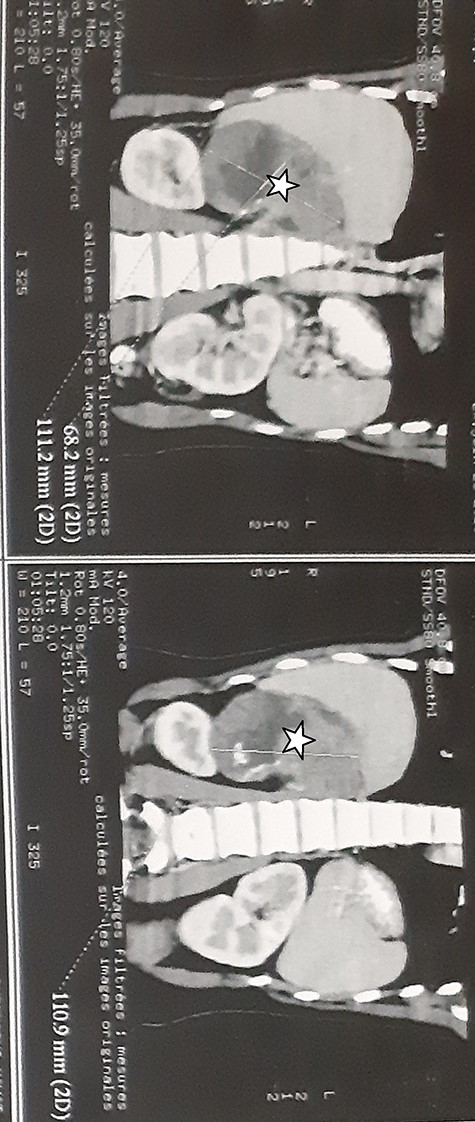

A 27-year-old woman presented with a 6 months history of a right flank pain and a moderate weight loss. She had no remarkable medical history. Upon physical examination, she had stable vital signs, without adrenal hormonal hypersecretion’s signs. The patient’s blood cell counts, serum electrolyte levels, renal and liver functions, 24-h urinary catecholamines, cortisol, testosterone, dihydroxyepiandrosterone sulfate and aldosterone levels were all within normal limits. Abdominal computed tomography (CT) scan showed a 12.5 × 9 × 7.5 cm tissular heterogeneous mass, with irregular borders, of the right adrenal gland, with calcifications (Fig. 1). The routine staging was negative for metastases.

Abdominal CT scan showed a 12.5 × 9 × 7.5 cm tissular heterogeneous mass, with irregular borders, located in the right adrenal gland (white star).